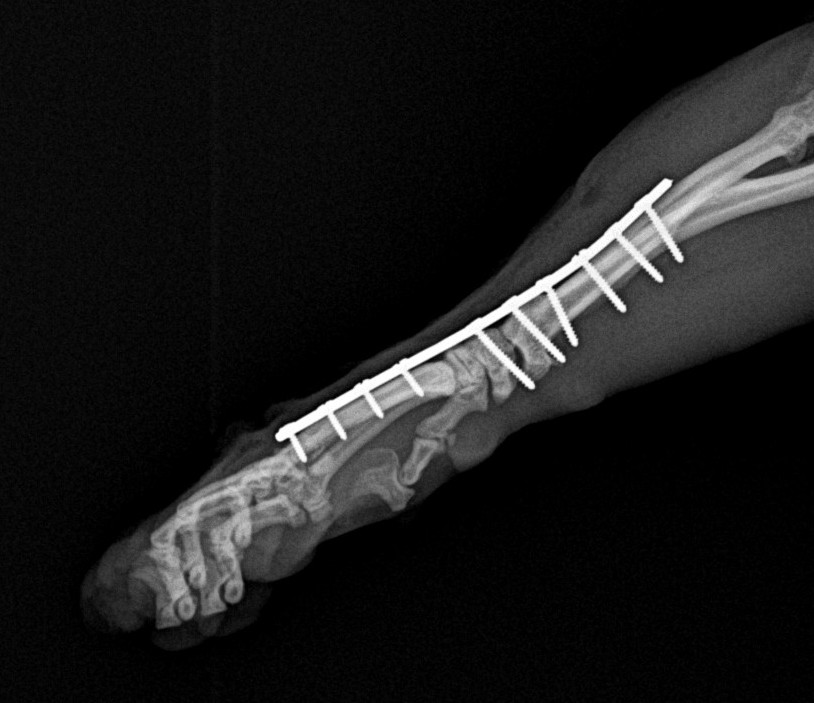

本症例では関節の安定性回復が困難と判断し、手根関節固定術を実施しました。

関節面の処理を行った上で、適切な角度で整復し、プレートによる内固定を行いました。